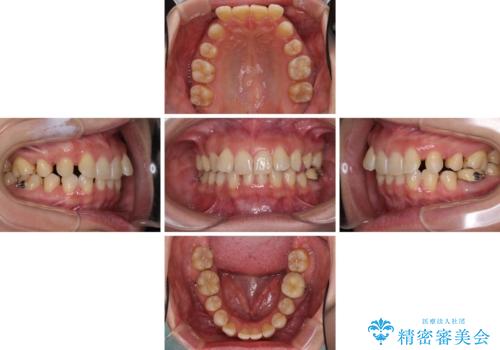

下顎2前歯の欠損 インビザラインによる抜歯矯正

- 下顎前歯欠損による歯列不正を気にして来院された患者様です。

下顎の歯列が小さく、下顎前歯が隠れてしまう過蓋咬合(ディープバイト)であったため、